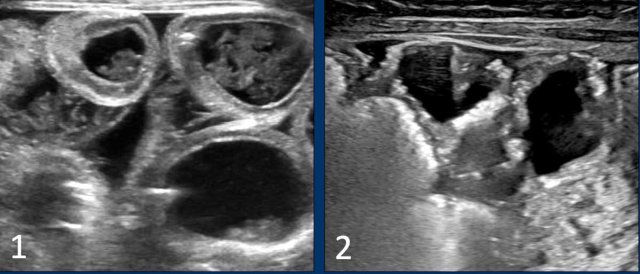

Images

- Bubbly lucencies due to lactobezoar in the right lower quadrant in an infant with milk curd syndrome. The finding may cause concern for pneumatosis intestinalis.

- Ultrasound demonstrates healty bowel, there is no pneumatosis intestinalis, but there are clearly thick intraluminal contents.